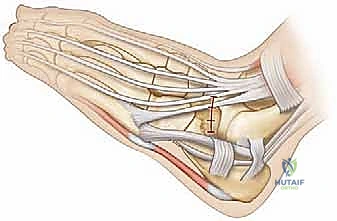

- التخدير والتحضير: تتم العملية تحت التخدير العام أو النصفي. يتم استخدام عاصبة (Tourniquet) لتقليل النزيف وضمان رؤية واضحة جداً للحقل الجراحي.

- الشق الجراحي: يُجري الدكتور هطيف شقاً جراحياً دقيقاً (شق أولييه - Ollier's incision) على الجانب الخارجي للقدم فوق منطقة الالتصاق مباشرة، مع الحرص الشديد على حماية الأعصاب والأوتار المحيطة باستخدام تقنيات الجراحة الميكروسكوبية.

- تحديد وعزل الالتصاق: يتم إبعاد العضلات والأوتار بلطف للوصول إلى الجسر العظمي الذي يربط بين العقب والعظم الزورقي. يتم تحديد حواف الالتصاق بدقة متناهية.

- الاستئصال العظمي الدقيق: باستخدام أدوات جراحية دقيقة (Osteotomes) ومناشير عظمية متطورة، يقوم الدكتور هطيف بإزالة الجسر العظمي بالكامل. يتم استئصال الالتصاق على شكل "مستطيل" لضمان إزالة مساحة كافية تمنع احتكاك العظمتين مجدداً وتسمح بحركة حرة.

- منع عودة الالتصاق (Interposition): هذه هي الخطوة الحاسمة التي تميز الجراح الخبير. لمنع العظم من النمو والالتصاق مرة أخرى، يجب وضع "حاجز" في الفراغ الذي تم إنشاؤه. يقوم الدكتور هطيف باستخدام جزء من عضلة مجاورة (Extensor Digitorum Brevis) أو قطعة من النسيج الدهني الحر، وتثبيتها بخيوط جراحية أو مثبتات دقيقة داخل الفجوة العظمية.

- الإغلاق: يتم غسل الجرح جيداً وإغلاق الطبقات والأنسجة بخيوط تجميلية لتقليل الندبات.